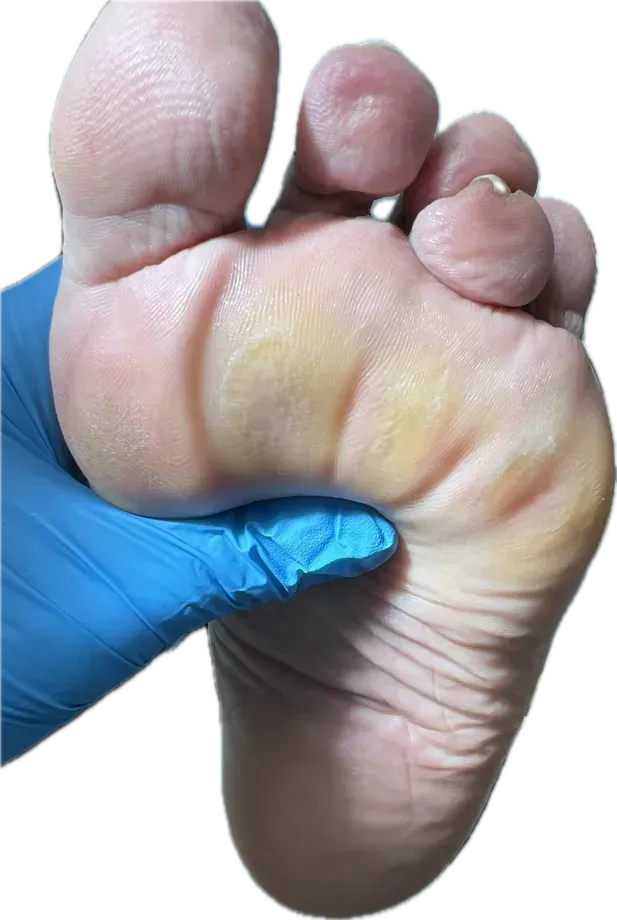

Callosidades y Sobrepresiones

Las callosidades profundas son uno de los problemas más frecuentes en el pie diabético. Se producen por sobrepresión mantenida en zonas de apoyo. En pacientes diabéticos, estas callosidades pueden evolucionar a lesiones preulcerosas si no se tratan adecuadamente.

- Atrofia del panículo adiposo plantar: la almohadilla grasa que protege el antepié se reduce